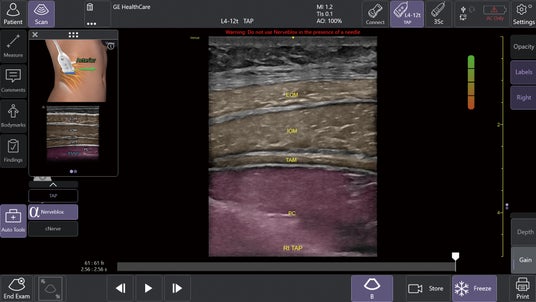

1.AIツール Nerveblox(ナーブブロックス)で神経ブロック手技を効果的にサポート

AIを用いて開発されたNervebloxは、区域麻酔に用いられる標準的な12種類の神経ブロック部位に対して、神経および周囲組織(筋肉・血管・骨・筋膜など)をリアルタイムに認識し、ハイライト表示する機能です。

本機能は、画像クオリティを評価するQuality Meter、プローブの向きをガイドするOrientation表示、組織を色分けするカラーオーバーレイ、解剖構造名を示すアナトミカルラベル、理想的なプローブ位置を提示する模式図ガイド等を備え、走査者のエコー経験レベルに依存しない、より安定した神経描出をサポートします。

この機能により、麻酔科、救急科、集中治療科、整形外科など多くの診療科において、神経ブロック時の解剖学的構造の認識や視認性が高まることが期待され、よりスムーズな判断や手技をサポートします。

Nervebloxによる神経ブロックのサポート (中央)Anatomical Labeling: 画像上に解剖学的ラベルを略語形式で表示 (右上)Quality Meter:表示画像の品質をリアルタイムで評価して色分け表示